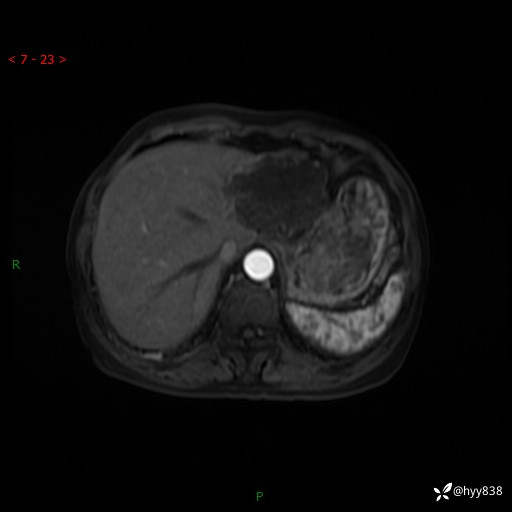

辅助检查:MRI

肝脏MRI平扫(同反相位)

T2WIfs+DWI

增强(动脉期+静脉期+延迟期)